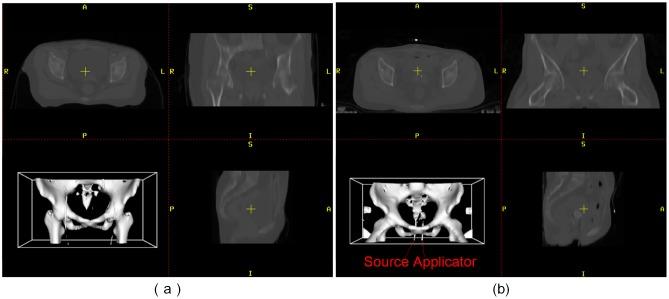

The combination external-beam radiotherapy and high-dose-rate brachytherapy is a standard form of treatment for patients with locally advanced uterine cervical cancer. Personalized radiotherapy in cervical cancer requires efficient and accurate dose planning and assessment across these types of treatment. To achieve radiation dose assessment, accurate mapping of the dose distribution from HDR-BT onto EBRT is extremely important. However, few systems can achieve robust dose fusion and determine the accumulated dose distribution during the entire course of treatment. We have therefore developed a toolbox (FZUImageReg), which is a user-friendly dose fusion system based on hybrid image registration for radiation dose assessment in cervical cancer radiotherapy. The main part of the software consists of a collection of medical image registration algorithms and a modular design with a user-friendly interface, which allows users to quickly configure, test, monitor, and compare different registration methods for a specific application. Owing to the large deformation, the direct application of conventional state-of-the-art image registration methods is not sufficient for the accurate alignment of EBRT and HDR-BT images. To solve this problem, a multi-phase non-rigid registration method using local landmark-based free-form deformation is proposed for locally large deformation between EBRT and HDR-BT images, followed by intensity-based free-form deformation. With the transformation, the software also provides a dose mapping function according to the deformation field. The total dose distribution during the entire course of treatment can then be presented. Experimental results clearly show that the proposed system can achieve accurate registration between EBRT and HDR-BT images and provide radiation dose warping and fusion results for dose assessment in cervical cancer radiotherapy in terms of high accuracy and efficiency.